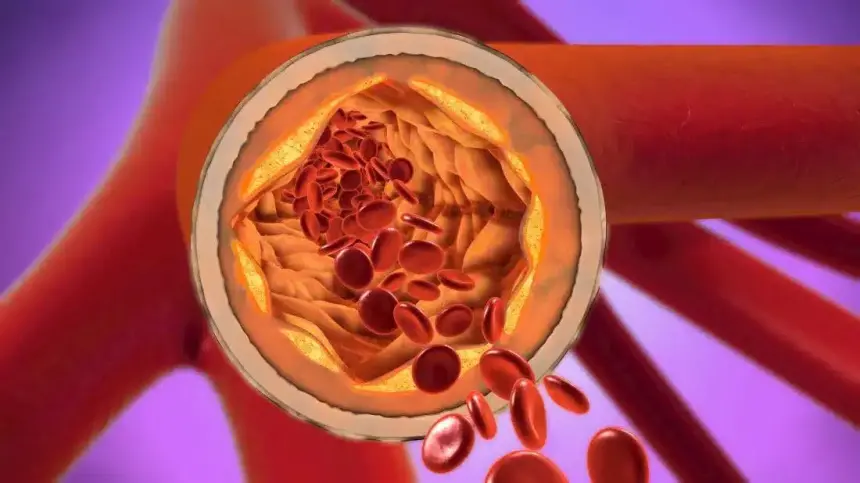

Alzheimer hastalığıyla ilgili çarpıcı bir araştırma yayımlandı. ABD merkezli UPI’nin aktardığına göre, bilim insanları kötü kolesterol olarak bilinen LDL seviyelerinin düşüklüğü ile demans riskinde azalma arasında güçlü bir ilişki tespit etti. Araştırmada, 300 bin kişilik geniş bir veri kümesi kullanıldı ve katılımcıların yıllar boyunca sağlık durumları incelendi. Bulgular, uzun süredir kalp-damar sağlığı için tehdit kabul edilen kötü kolesterolün, sinir sistemi üzerindeki etkilerinin sanıldığından daha karmaşık olduğunu gösteriyor.

Araştırmayı yürüten bilim insanları, LDL seviyeleri daha düşük olan bireylerin, özellikle yaşlılıkta Alzheimer’a yakalanma ihtimalinin önemli ölçüde daha az olduğunu belirledi. LDL düşüklüğüyle bilişsel işlevlerin korunması arasında kurulan bu bağ, demansla mücadelede yeni yaklaşımların kapısını aralayabilir. Özellikle genetik yatkınlığı bulunan kişilerde kötü kolesterolün azaltılmasının, beyin sağlığını koruma açısından beklenenden daha büyük fayda sağlayabileceği düşünülüyor.

Çalışmada yer alan uzmanlar, bu bulguların henüz kesin bir tedavi yöntemi anlamına gelmediğini, ancak önleyici yaklaşımlar açısından dikkate alınması gerektiğini vurguladı. Ayrıca kolesterol dengesinin tamamen bozulmasının başka sağlık sorunlarına yol açabileceği konusunda da uyarıda bulunuldu.